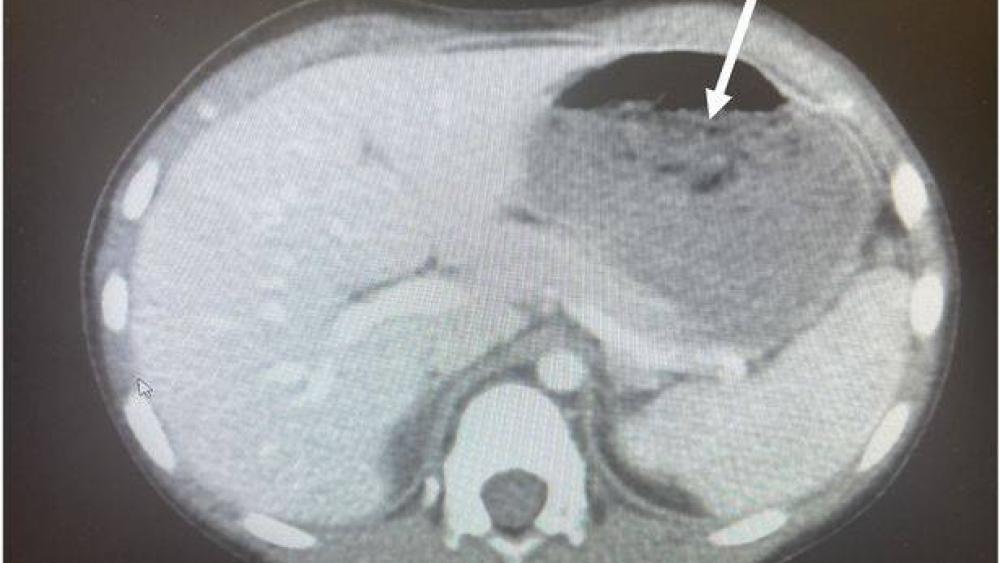

ابتلع طفل (5 سنوات) من ولاية أوهايو الأمريكية 40 قطعة علكة أصابته بتشنجات وإسهال حاد نقل على إثرها إلى غرفة الطوارئ. وأظهرت الأشعة المقطعية وجود كتلة كبيرة من العلكة في معدته شغلت 25% من مساحة المعدة، ويطلق على هذه الحالة اسم «بازهر».